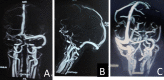

A 35-year-old man with a history of multiple substances abuse (alcohol, tobacco and cannabis) presented with acute, severe, holocranial headache associated with nausea and few episodes of vomiting followed by acute onset Broca-type aphasia with intact comprehension from next day, without any other focal neurodeficits, seizure or altered sensorium. Neurological examination was marked by Broca-type aphasia and failure in convergence reaction bilaterally, rest unremarkable. Brain imaging revealed lesions in bilateral thalamus, while magnetic resonance venography showed multiple flow voids in posterior part of superior sagittal sinus and bilateral transverse sinus. A diagnosis of cerebral venous sinus thrombosis was made. Subsequent investigations revealed decreased levels of protein C, protein S and antithrombin III. The patient was started on anticoagulation to which his headache and aphasia recovered completely after 8 and 12 days of therapy, respectively. He is being continued on anticoagulation and is following-up with us for past 4 months uneventfully.